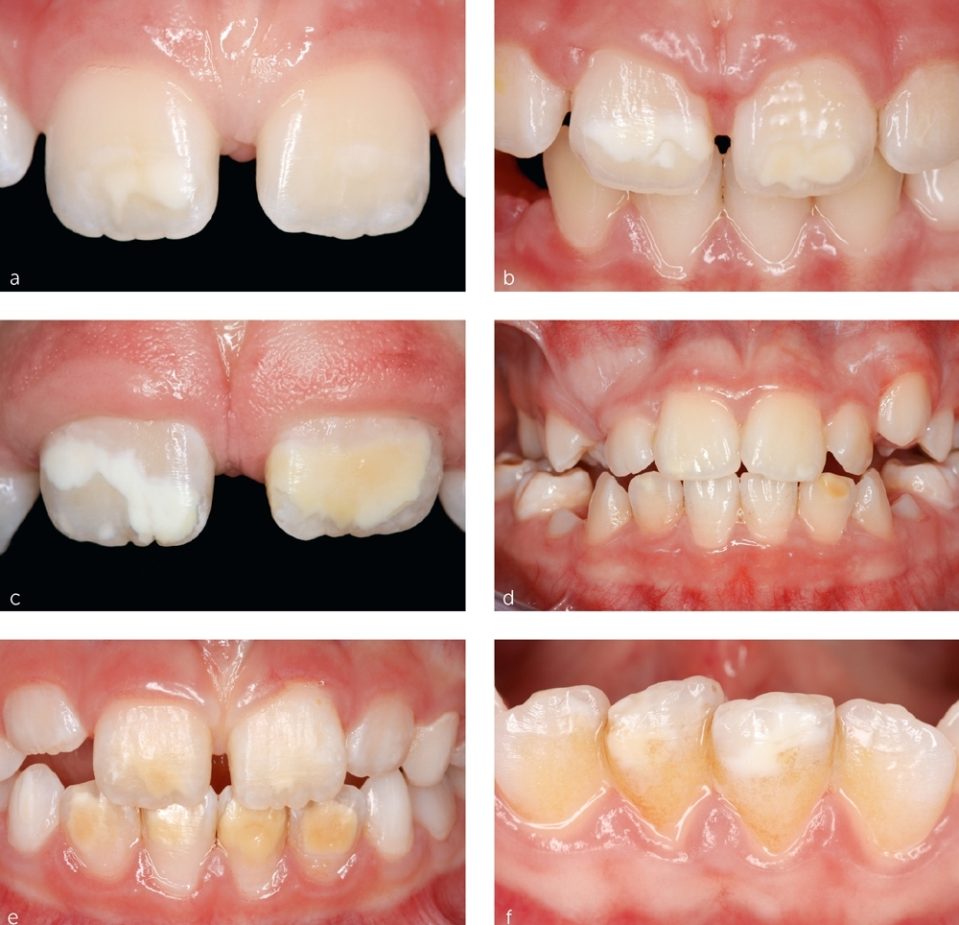

Hypomineralisation is a developmental condition that affects the enamel – the hard outer layer of the tooth. It occurs when the enamel does not form properly, resulting in teeth that may appear:

- Creamy white, yellow, or brown

- Rough or chalky in texture

- Soft or crumbly at the edges

- More vulnerable to decay or breakdown

In children, hypomineralisation most commonly affects the first permanent molars and the front adult teeth (incisors). This specific pattern is known as Molar-Incisor Hypomineralisation (MIH).

In some cases, baby teeth can also be affected—a condition known as Deciduous Molar Hypomineralisation (DMH)—which can be an early indicator of MIH developing later.

Hypomineralisation is a developmental defect of tooth enamel that occurs when the enamel doesn’t form properly. It most commonly affects the first permanent molars and incisors, but can occasionally involve other teeth. This condition results in teeth that appear chalky, discoloured (white, yellow, or brown patches), and are more prone to sensitivity, wear, and decay.